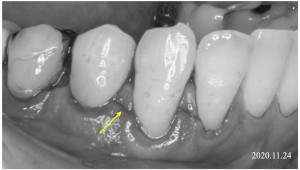

※切開

手術時の切開について

上の写真で矢印で示している部分は、手術の際に行う切開線です。

この切開線を基準として、歯ぐきの処置を次のように行います。

まず、切開線より上の歯と歯の間の歯ぐき(歯間乳頭)の部分では、歯ぐきの表面にある上皮(表面の組織)を取り除く処置を行います。これは、移動させる歯ぐきが周囲の組織となじみやすくするための準備となります。

一方で、切開線より下の部分の歯ぐきは、歯ぐきを丁寧に剥離し、歯の方向(歯冠側)へ移動できるように処置を行います。

このような処置を行うことで、歯ぐきを歯の方向へ移動させ、露出している歯の根の部分を覆うことを目指します。